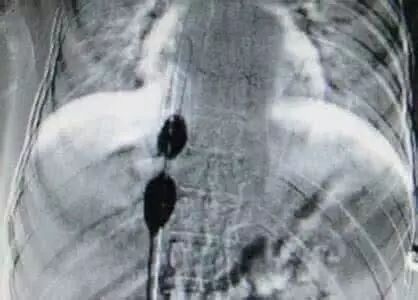

如果临床怀疑HVOO,则应进行肝静脉/下腔静脉血管造影(血管造影是诊断HVOO金标准,不仅可明确梗阻部位/性质,还可测定梗阻两端的静脉压力差,从而直接反映狭窄处血流动力学变化)。临床医生应该综合考虑患者的临床表现、静脉造影结果(狭窄程度)及梗阻两端压力差等多方面因素,做出正确的诊断及是否治疗的判断。一般来说,以梗阻两端静脉压力差>3mmHg为标准判断有无HVOO及介入治疗是否有效。

球囊扩张/支架植入已成为肝移植术后HVOO的主要治疗方法,临床研究报道,技术成功率为91%~100%,临床成功率为73%~100%,技术不成功多与肝静脉过度扭曲、成角、严重狭窄或闭塞以及介入治疗入路选择不当有关(单纯球囊扩张对静脉扭转、成角和外在压迫作用甚微)。另外,考虑到移植肝的生长可能导致植入支架与肝静脉大小不匹配而影响肝静脉流出道,对儿童肝移植进行支架植入治疗仍存在争议(但也有报道称,儿童肝移植中的供肝来源于成人,故建议植入与成人肝静脉相匹配的支架);对于下腔静脉梗阻为主的HVOO支架植入是首选的介入方法。而一旦HVOO持续时间过长,肝内淤血情况逐渐加重导致移植肝出现肝纤维化、肝硬化,甚至出现上消化道出血、肝功能衰竭等终末期肝病的临床表现,则需考虑再次肝脏移植手术